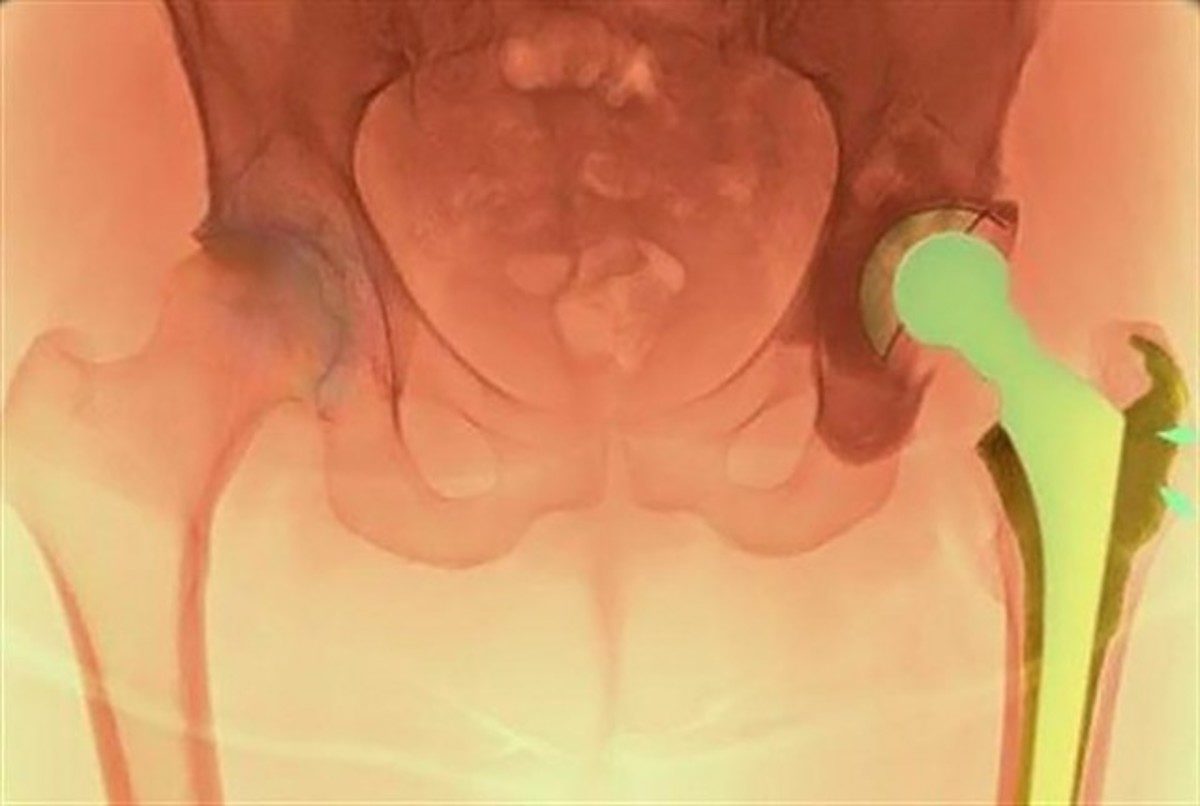

Η Κλινική Μεγάλων Αρθρώσεων του Ιατρικού Κέντρου Αθηνών, με Διευθυντή τον κ. Ιωάννη Τσαρούχα, έχει πραγματοποιήσει με επιτυχία σημαντικό αριθμό αναθεωρήσεων προβληματικής ολικής αρθροπλαστικής του ισχίου, εφαρμόζοντας την τεχνική ελάχιστης επεμβατικότητας ASI (Anterior Supine Intermuscular). Οι ασθενείς που υποβάλλονται στην επέμβαση αυτή εξασφαλίζουν την πολυετή ομαλή λειτουργία της πρόθεσής τους και διατηρούν υψηλό επίπεδο ποιότητας ζωής.

Η ολική αρθροπλαστική ισχίου είναι μία από τις πιο επιτυχημένες χειρουργικές επεμβάσεις στην ορθοπαιδική. Ωστόσο, ένας σημαντικός αριθμός ασθενών υποβάλλεται σε αναθεώρησή της (δεύτερη επέμβαση/επανεπέμβαση) λόγω μηχανικών προβλημάτων (χαλάρωση ή φθορά της πρόθεσης, κακή τοποθέτηση), μικροβιακών λοιμώξεων ή κατάγματος κοντά στην πρόθεση. Σε αρκετούς από αυτούς τους ασθενείς η αναθεώρηση μπορεί να μην έχει τα επιθυμητά αποτελέσματα και έτσι θα χρειαστεί να υποβληθούν σε επέμβαση αναθεώρησης για δεύτερη, τρίτη, ακόμα και τέταρτη φορά. Σημειώνεται ότι, οι επεμβάσεις αναθεώρησης στο ισχίο απαιτούν μεγάλες τομές, σοβαρές κακώσεις στα μαλακά μόρια και έντονη απώλεια αίματος, ενώ συνοδεύονται από αυξημένο ποσοστό επιπλοκών σε σχέση με την αρχική επέμβαση.

Η πρωτοποριακή μέθοδος ASI είναι η πιο σύγχρονη μέθοδος ελάχιστης επεμβατικότητας και χρησιμοποιείται με μεγάλη επιτυχία σε περιπτώσεις που είναι αναγκαία η αναθεώρηση της κοτυλιαίας πρόθεσης. Ορισμένα από τα βασικά πλεονεκτήματα της μεθόδου ASI, είναι η ελαχιστοποίηση του κίνδυνου για μετεγχειρητικά εξαρθρήματα, η εξάλειψη του κίνδυνου για μετεγχειρητική ανισοσκελίακαθώς και η πρόσβαση στην παλαιά πρόθεση και η τοποθέτηση και ο προσανατολισμός της νέας με μεγαλύτερη ευκολία και αξιοπιστία. Παράλληλα, μειώνεται ο χρόνος αποκατάστασης και αποφεύγονται οι επιπλοκές που συνοδεύουν τη μακρά περίοδο ανάρρωσης μετά από εκτεταμένες προσπελάσεις του ισχίου, ενώ δεν χρειάζεται μετάγγιση.